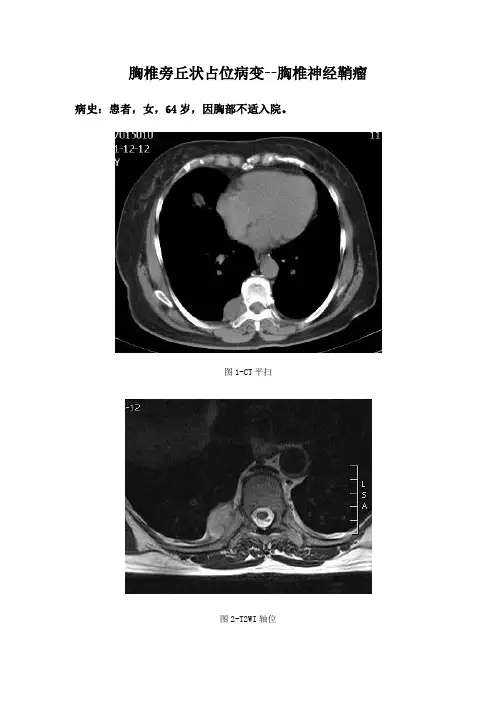

胸椎旁丘状占位病变--胸椎神经鞘瘤病史:患者,女,64岁,因胸部不适入院。

图1-CT平扫图2-T2WI轴位图3-T1WI轴位压脂图4-T2WI矢状位压脂图5-T1WI冠状位压脂基础解剖影像:图6图6为所示病例同层面肺窗和纵膈窗的融合CT图片,黄色箭头所示为胸椎骨质高密度影,棕色箭头所示为椎弓及棘突骨质高密度影,蓝色箭头所示为椎间孔低密度影与椎管相通。

图1图2图3图4图5图1为CT轴位及图2-5为MRI轴位、矢状位、冠状位:图1白色箭头所示可见第8胸椎右旁丘状软组织密度影,密度不均。

图2白色箭头见病变呈稍长T2信号,呈宽基底贴于胸膜,临近后肋骨质边缘受压分界不清。

图3-5黄色箭头见病变呈哑铃型与椎管相通,T1压脂像呈稍高信号,T2压水压脂像呈高信号。

影像描述:CT示第8胸椎右侧脊柱旁沟见丘状占位病变,呈宽基底贴于胸膜,临近肋骨骨质受压。

MRI示病变呈稍长T1长T2信号,压水压脂像呈高信号,边界清晰,病变呈舌状向椎管内部延伸,相邻骨质边缘受压,相邻脊神经增粗,信号增高。

影像诊断:第8胸椎旁占位病变,考虑神经源性肿瘤,以神经鞘瘤可能性大。